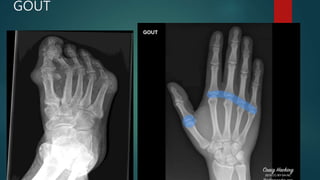

GOUT

• #84 Punched-out juxta-articular erosions of the first and fifth metatarsal heads with overhanging edges are typical for gout. Overlying soft tissue swelling and increased density represent tophi.